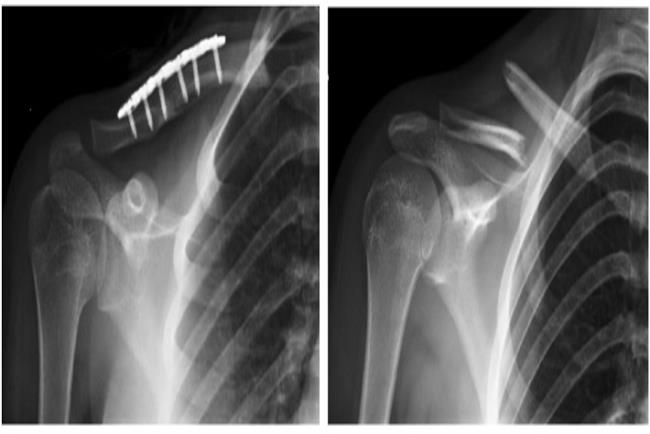

שבר בעצם הבריח בתזוזה וקיצור ניכרים, שטופל בניתוח לשחזור וקיבוע פנימי ע"י פלטה וברגים. בצילום מימין ניתן להתרשם מאופי השבר. בצילום משמאל ניתן לראות את הכתף ועצם הבריח לאחר הניתוח.